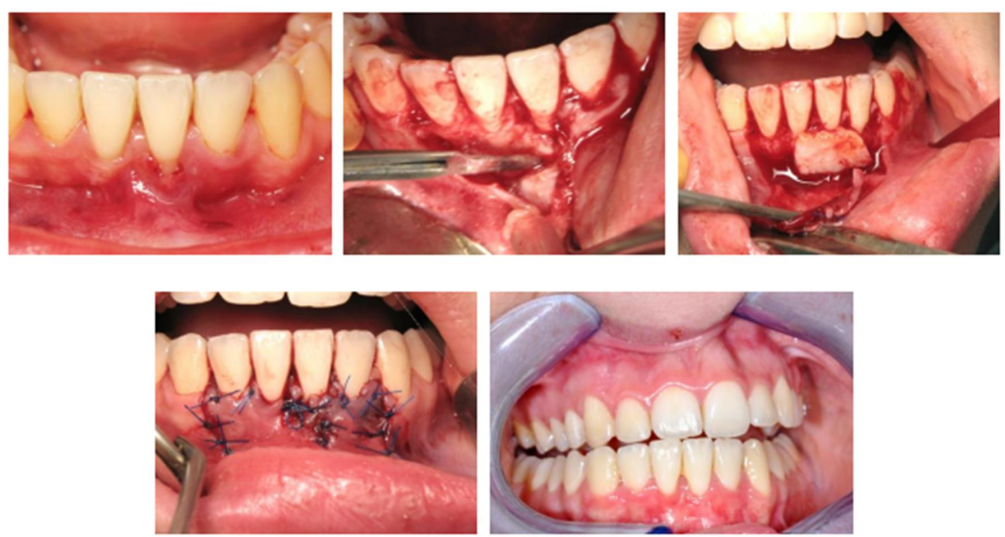

Greffe de conjonctif enfoui (de gauche à droite) : Vue Préopératoire avec récession sur 31 ; réalisation du lambeau, suture du greffon au site receveur ; Traction coronaire du lambeau pour recouvrir le greffon et sutures ; Vue à 2 mois postopératoire.